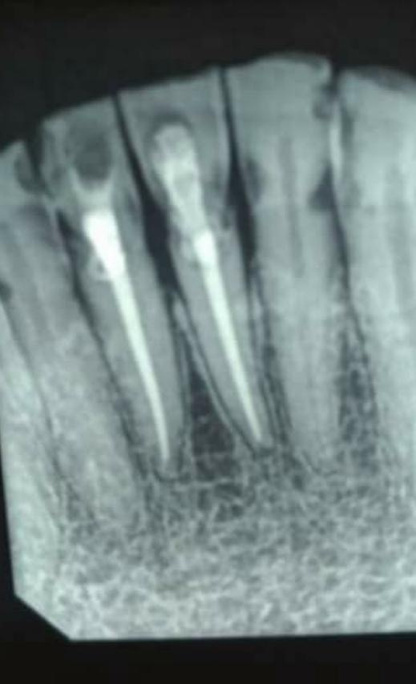

tipos de atendimentos - endodontia

Tratamento rápido e sem dor, combinando técnicas avançadas e tecnologia de ponta para garantir a preservação dos dentes e o sucesso a longo prazo.